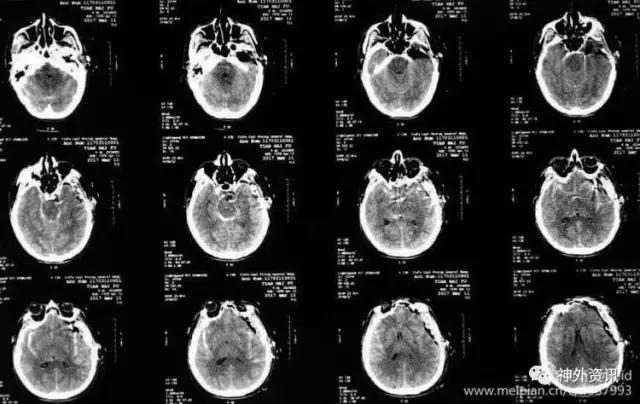

CT平扫提示SAH,鞍上池和双侧外侧裂池广泛均匀分布。

术后复查头CT显示手术效果满意。